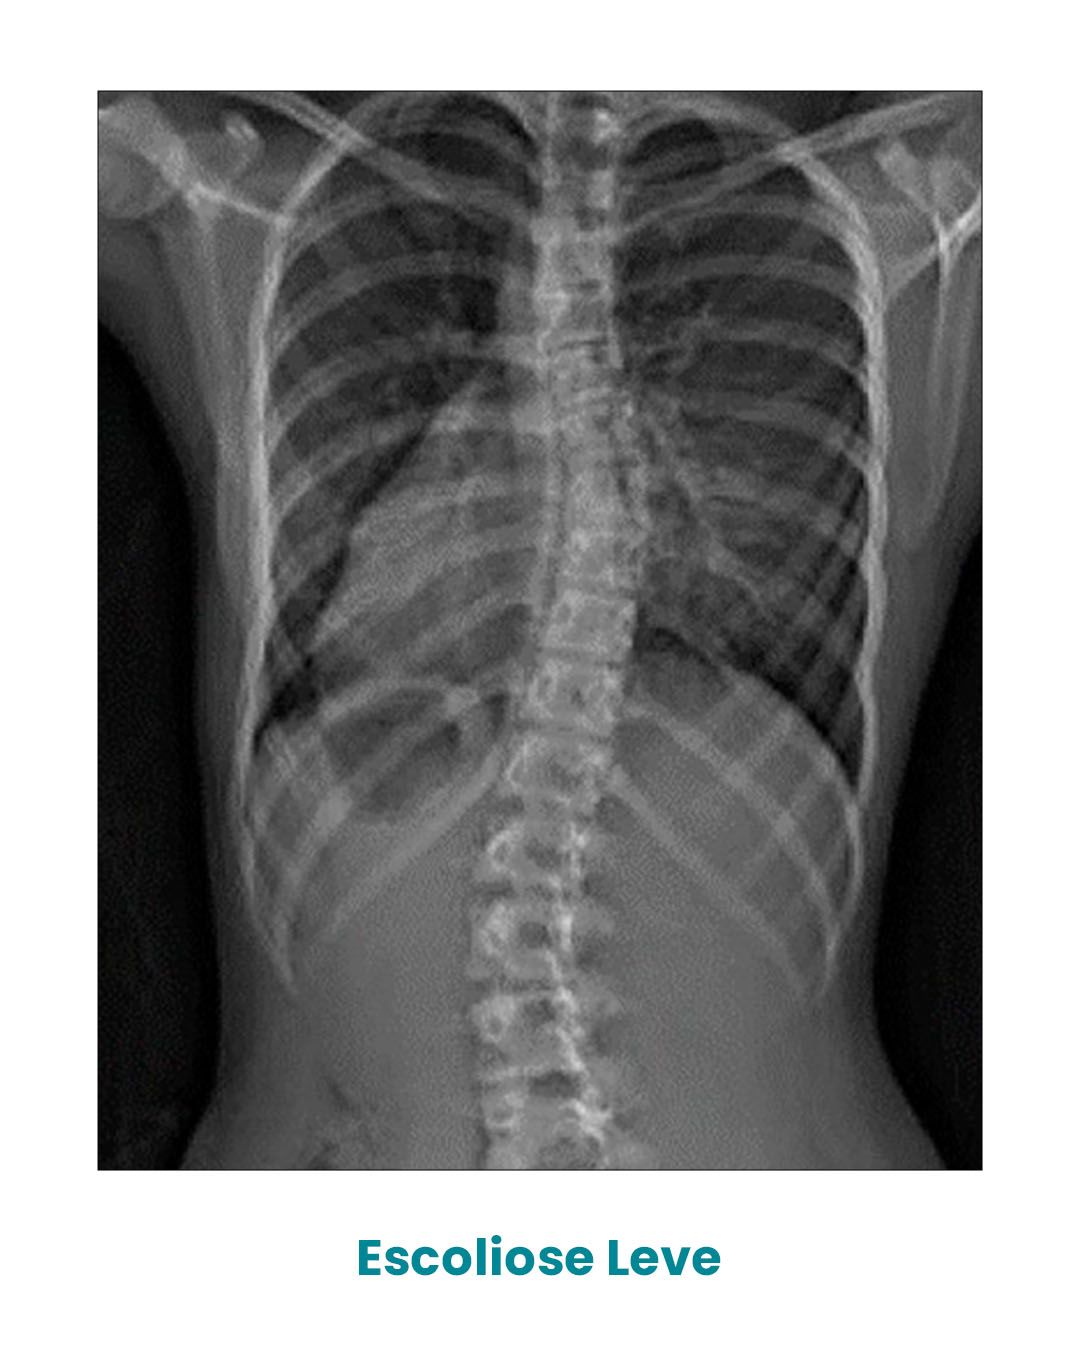

Após o diagnóstico, através de um simples Raio-X da coluna vertebral, podemos classificá-la em três tipos de acordo com o ângulo de Cobb.

Quando o ângulo de Cobb está entre 10o e 20 o estamos diante de uma escoliose leve, comumente tratável com exercícios fisioterapêuticos específicos para escoliose.